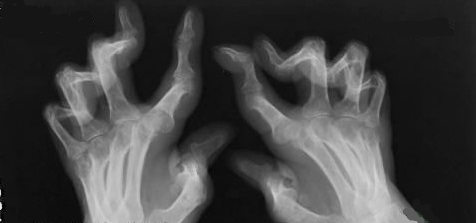

类风湿关节炎在手、足关节有哪些常见的关节畸形?

类风湿关节炎如果病情未得到有效控制,滑膜炎长期持续存在的话,关节就容易出现变形。当病情进展到较后期,患者会被种类繁多的关节畸形所困扰,不仅影响美观,还会损害关节的正常功能,给患者生活造成极大不便。类风湿关节炎的关节畸形一般发生在手、足关节上,常见的有以下几种:

(1)手关节的畸形

天鹅颈畸形:手指的近端指间关节过伸,远端指间关节屈曲,侧面看像天鹅的颈部。

纽扣花畸形:手指的近端指间关节屈曲,远端指间关节过伸,整体看上去像纽扣花。

尺偏畸形:除了拇指外,其余四根手指的掌指关节都向小指方向偏斜。

望远镜畸形:指骨骨端吸收导致手指明显缩短,手指关节松弛不稳,可拉长或缩短,就像旧时候看戏用的小望远镜一样。